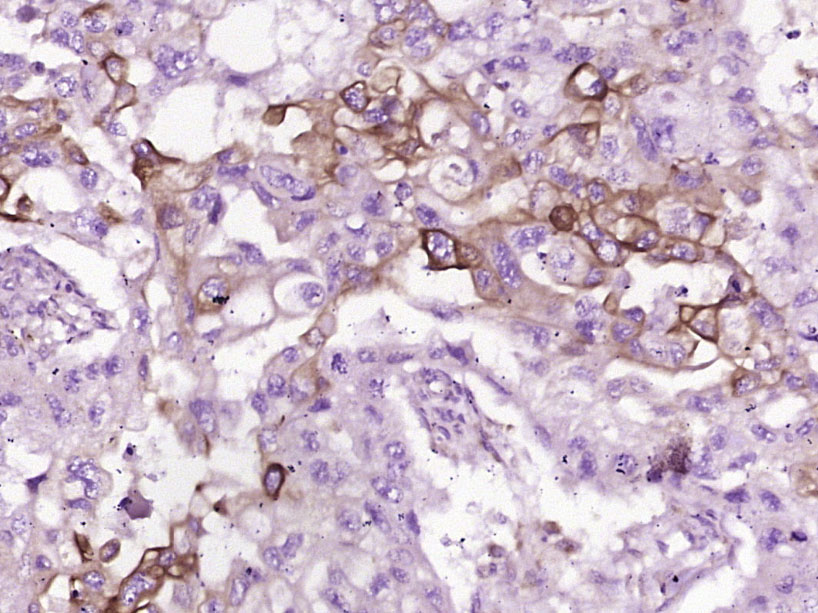

Paraformaldehyde-fixed, paraffin embedded (human skin cancer); Antigen retrieval by boiling in sodium citrate buffer (pH6.0) for 15min; Block endogenous peroxidase by 3% hydrogen peroxide for 20 minutes; Blocking buffer (normal goat serum) at 37°C for 30min; Antibody incubation with (FGFBP1) Polyclonal Antibody, Unconjugated (bs-1768R) at 1:400 overnight at 4°C, followed by operating according to SP Kit(Rabbit) (sp-0023) instructionsand DAB staining.